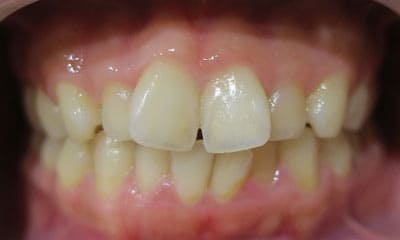

● 歯根が折れ保存不可の歯を抜歯して、そのスペースに八重歯を並べた症例

藤沢デンタルオフィスの虫歯や破折で抜歯後の部分矯正